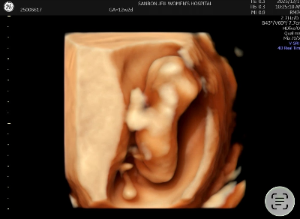

궁디 나온 입체 초음파 엄청 귀엽죠?ㅋㅋㅋ

원래 정자세로 잘 보여주다가 배를 흔드니까 저렇게 뒤돌아버렸어요.

코뼈, 목투명대 다 정상